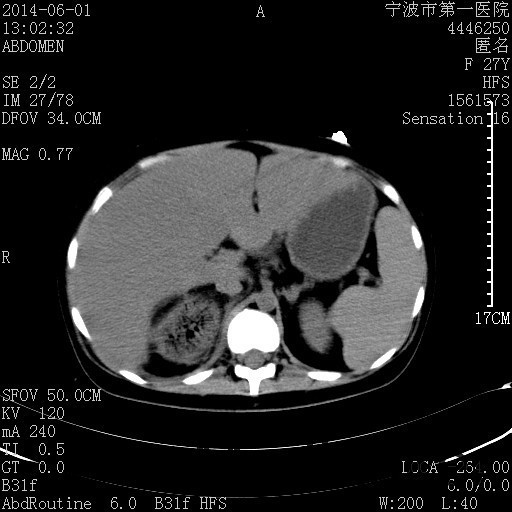

患者,女,27岁,因“右下腹疼痛伴呕吐2天”入院 患者无明显诱因出现右下腹疼痛伴呕吐、发热,体温最高39度,急诊CT示:右肾集气,考虑气性肾盂肾炎。

查体: 右肾区叩击痛,右下腹压痛,无反跳痛。 辅助检查: 空腹血糖9.7mmo/L,餐后血糖18mmol/L 血常规:白细胞 11.3*109/L, 中性百分比 77.4%, 血红蛋白 8g/L, 血小板 319*109/L 尿常规 WBC+++ 生化:白蛋白 37.5g/L,肝肾功能正常 泌尿系CT:右肾集气

诊断为“气性肾盂肾炎,感染性休克,糖尿病酮症酸中毒” 血、尿、脓液培养均示“克雷伯杆菌” 入院第2天行“右双J管置入术” 入院第3天、7天行“右肾穿刺造瘘术” 入院1月行“右肾切除术” 术后顺利康复出院。